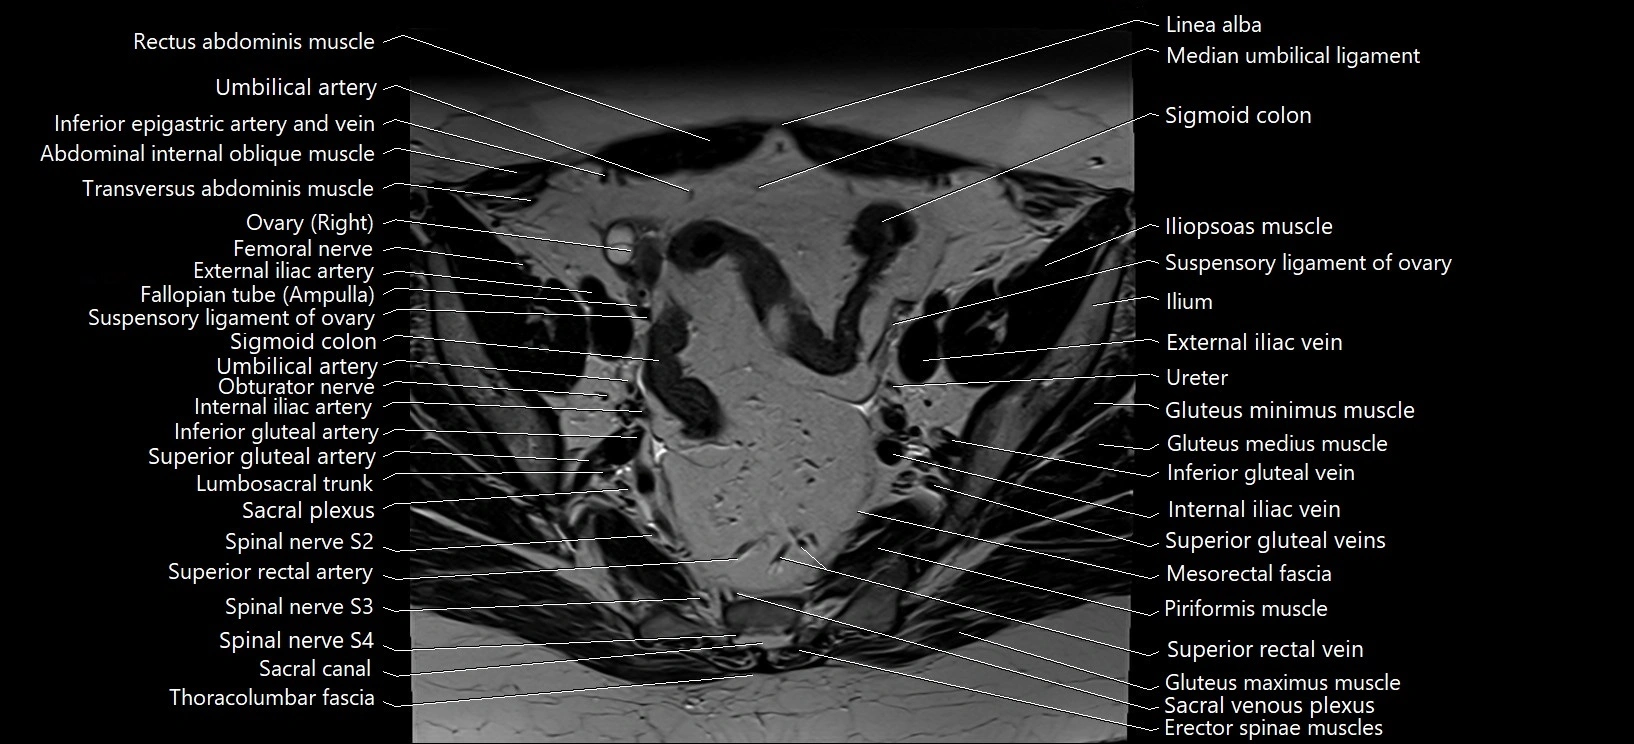

- Common iliac vein

- Erector spinae muscles

- External iliac artery

- External iliac vein

- Femoral nerve

- Gluteus maximus muscle

- Gluteus medius muscle

- Gluteus minimus muscle

- Ileum

- Iliopsoas muscle

- Inferior gluteal artery

- Inferior gluteal vein

- Inferior mesenteric artery (IMA)

- Internal iliac artery

- Internal iliac vein

- Linea alba

- Lumbosacral trunk

- Median umbilical ligament

- Mesorectal fascia

- Piriformis muscle

- Right ovary

- Sacral plexus

- Sacroiliac joint

- Sigmoid colon

- Spinal nerve S2

- Spinal nerve S3

- Spinal nerve S4

- Superior gluteal artery

- Superior gluteal veins

- Superior rectal artery

- Superior rectal vein

- Suspensory ligament of ovary

- Transversus abdominis muscle

- Umbilical artery